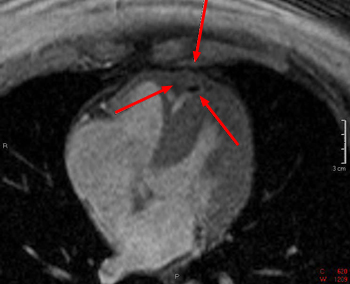

Primary malignancies of the pericardium are rare. The most common is primary pericardial mesothelioma. The pericardium is more commonly a site of metastases from lung, colon, and breast cancer. All metastatic tumors will typically enhance.

These spin echo (left) and gradient echo (right) images show a mass within the pericardium. It is somewhat heterogenous and is not consistent with a benign pericardial cyst. This patient was found to have a pericardial mesothelioma.